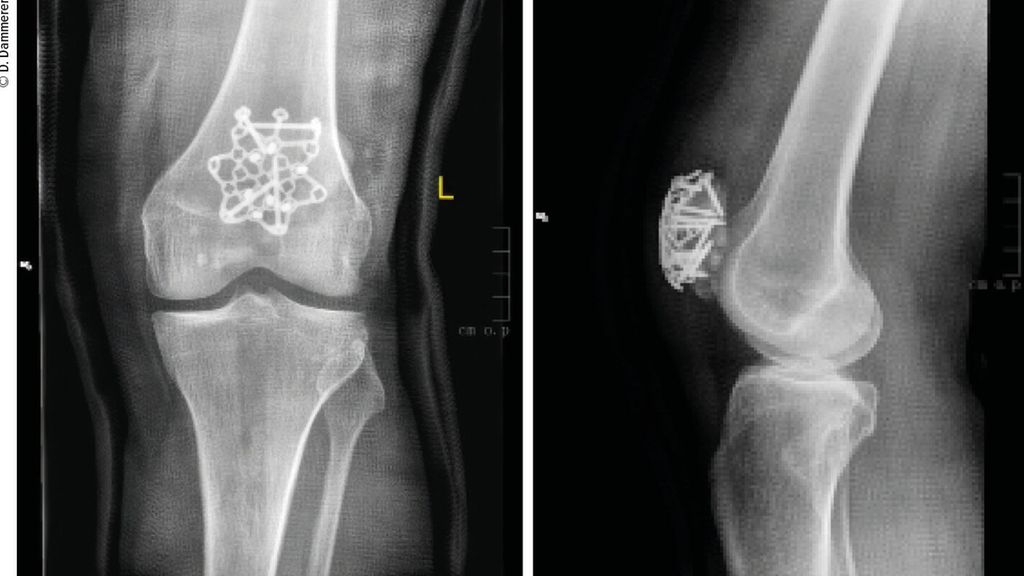

Abb. 1: Eine komplexe Mehrfragmentfraktur der Patella ergibt die Indikation zur operativen Versorgung

Abb. 2: Die operative Versorgung erfolgte mittels Sternplatte und zeigt ap und seitlich eine gute Reposition aller Frakturfragmente